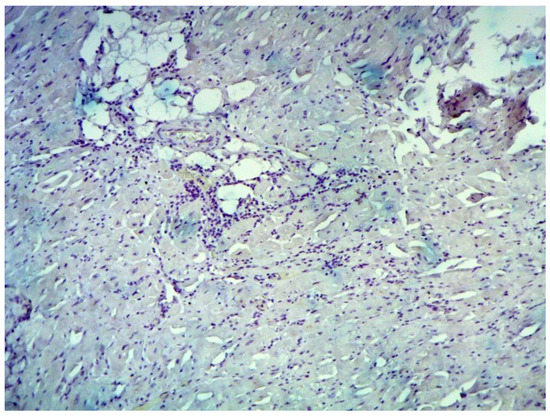

According to EMB results, no histological changes in the myocardium of the right ventricle (RV) were found in nine patients (13.4%). Fibrotic changes in the myocardium were detected in 26 cases (38.8%) including in predominantly perivascular fibrosis in 11 patients (42.3%), small focal fibrosis in eight patients (30.8%), and perimuscular fibrosis in seven patients (26.9%) (Figure 1, Figure 2 and Figure 3).

Figure 4. Endomyocardial infiltration with CD3+ lymphocytes. Immunohistochemical study, antibodies to the Epstein-Barr virus, ×200.

Jcm 12 01254 g004